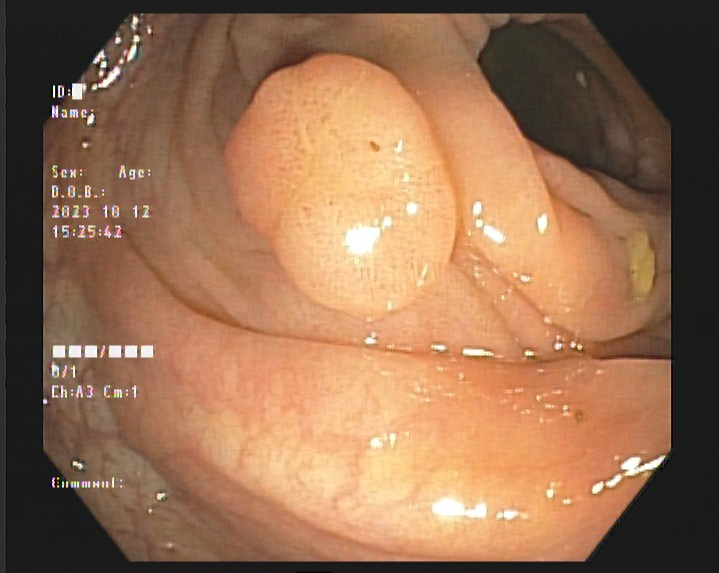

结肠良性肿瘤

结肠腺瘤